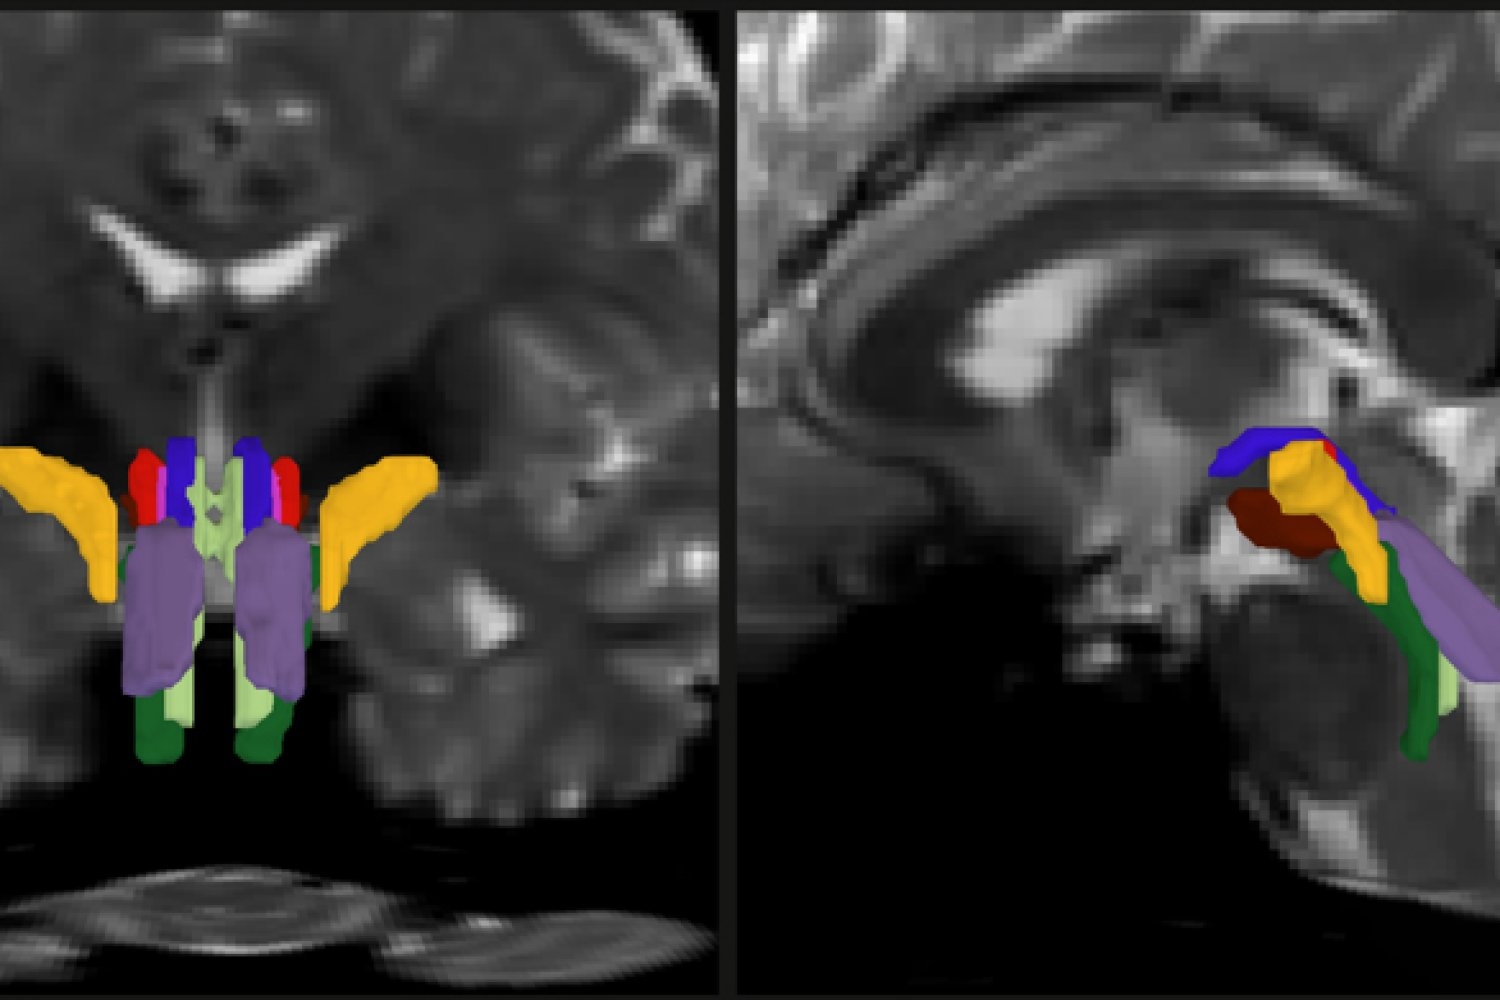

Researchers have developed a new way to resolve distinct bundles of nerve fibers in the brainstem. In this detail of a…

Opening a new window on the brainstem, a new tool reliably and finely resolves distinct nerve bundles in live diffusion MRI scans, revealing signs of injury or disease.

As part of his thesis work to better understand the neural mechanisms that underpin consciousness, Olchanyi wanted to develop an AI algorithm to overcome these obstacles. BSBT works by tracing fiber bundles that plunge into the brainstem from neighboring areas higher in the brain, such as the thalamus and the cerebellum, to produce a “probabilistic fiber map.” An artificial intelligence module called a “convolutional neural network” then combines the map with several channels of imaging information from within the brainstem to distinguish eight individual bundles.